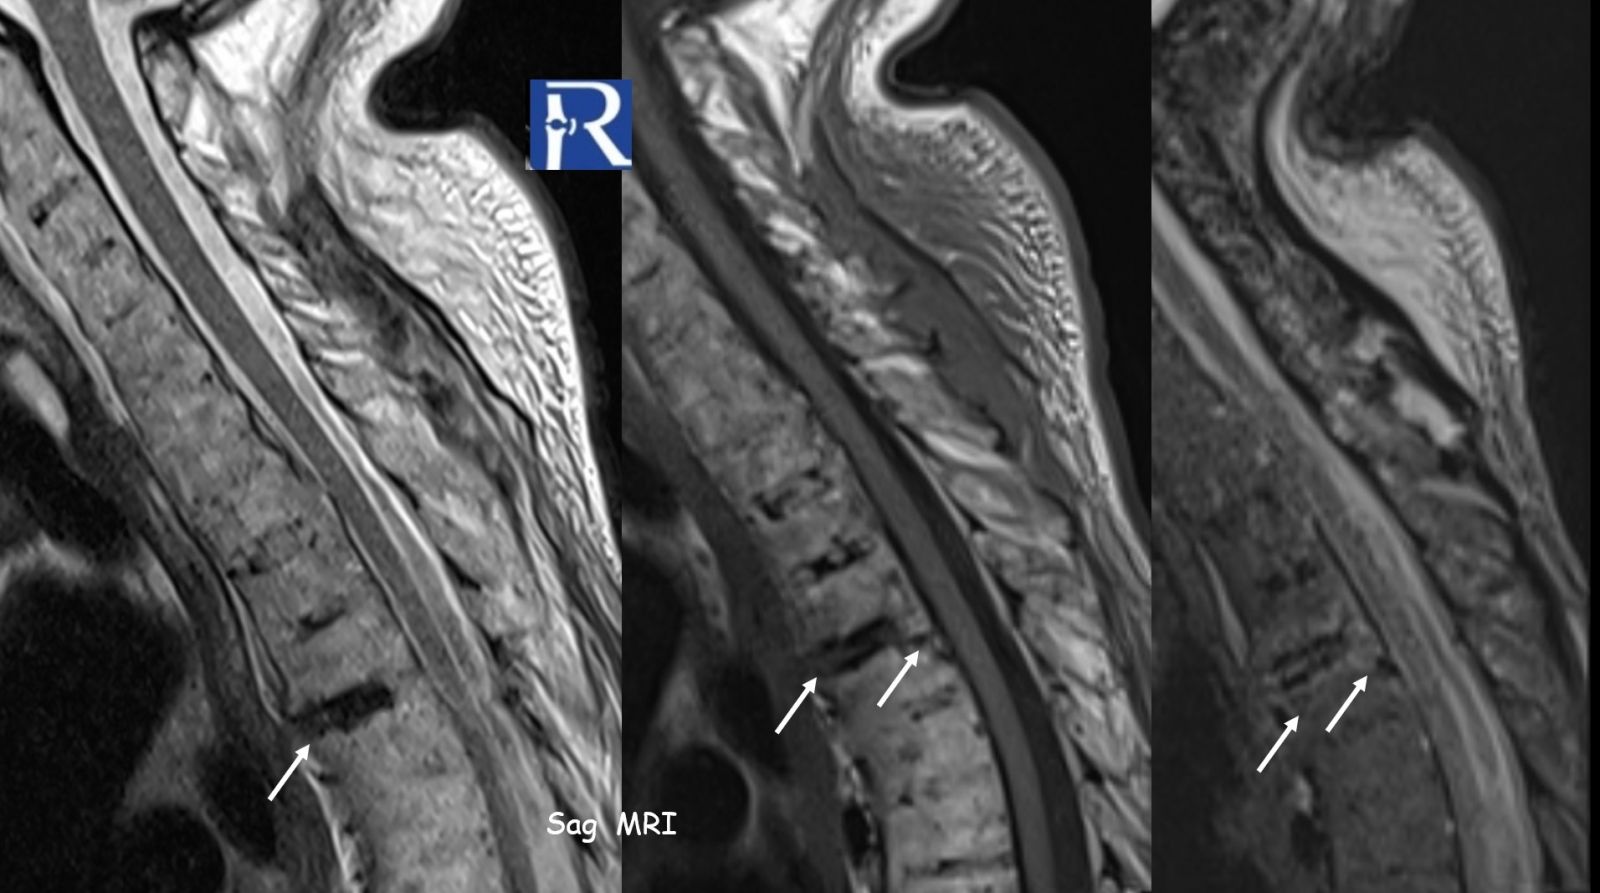

Imaging Findings

- At the T3–T4 level, a transdiscal fracture is observed

- Associated marrow edema and soft tissue changes on MRI

This represents a classic “chalk-stick fracture”, a transverse fracture through a rigid, ankylosed spine.

- MRI → evaluates:

- Bone marrow edema

- Ligamentous injury

- Spinal cord involvement